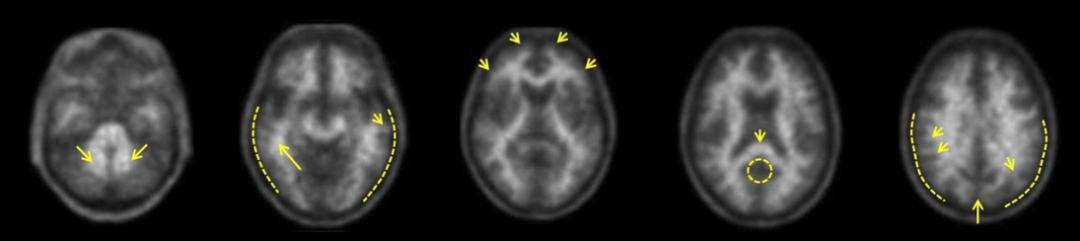

Neuraceq为一种脑β-淀粉样蛋白(Aβ)正电子发射断层扫描(PET)显像剂,是由德国Life Molecular Imaging (LMI)公司所研发,该显像剂通过PET/CT或PET/MRI设备进行PET成像,可对成年患者脑内β-淀粉样蛋白(Aβ)水平进行精准测定,以评估阿尔茨海默病(AD)导致认知功能下降的病因。

氟[18F]比他班注射液是一种18F标记的二苯乙烯衍生物,可与AD患者大脑皮层中的Aβ斑块特异性结合,不与组织中的Tau或α-突触核蛋白作用;氟[18F]比他班注射液通过18F核素产生正电子信号,由PET/CT或PET/MRI设备进行PET扫描,以PET图像检测大脑各区的Aβ斑块形成信号。